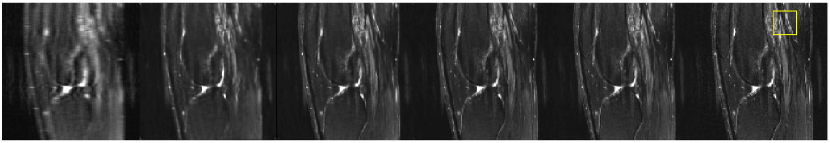

Fig. 2 compares the reconstructed images for Sag-T2 and Cor-T2 contrasts from different methods at AR=6. While ISTA-Net and pMRI-Net can largely remove the aliasing artifacts at this undersampling level, both methods yielded suboptimal reconstruction performance with noticeable image blurring in the reconstructed images. Our proposed STL can enable better reconstruction than ISTA-Net and pMRI-Net with improved image sharpness, due to its ability to cross-learn both image and k-space features, therefore better removing noises and artifacts and meanwhile preserving high-frequency image features. Our proposed MTML using meta-learning performs the best, outperforming all single-task learning methods. The pixel-wise error maps show that MTML has the smallest reconstruction errors compared to the fully-sampled reference, and the error is more homogeneous across the entire image domain for MTML. The zoom-in images further highlight the superb reconstruction performance of MTML where the tissue boundaries are better characterized at all tissue types (cartilage, meniscus, and muscle), and tissue texture, sharpness, and conspicuity are well-preserved. Similar comparisons of reconstructed images for the Sag-PD and Cor-PD sequences are shown in the Appendix, where MTML also consistently enables the best and most balanced performance on different types of contrast.